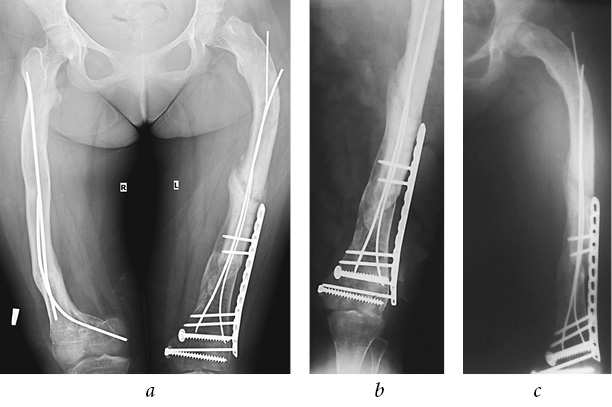

On September 24, 2016, the patient felt severe pain in her left femur while walking. She visited the primary care facility, where, according to the results of X-ray, a re-implant fracture of the left femur was diagnosed (Fig. 9 a).

Fig. 9. Reimplantation fracture of the left femur, lack of complete consolidation of the distal third of the shaft, frontal view (a); postoperative radiographs of the left femur, frontal view (b)

On September 29, 2016, the patient was taken to EMC. Due to the unstable nature of the fracture, displacement of fragments, severe pain, blood loss, and the need for early activation in order to prevent hypokinetic osteoporosis, surgical treatment was indicated.

After the standard preoperative preparation, the surgery was performed on the same day. Due to the lack of complete consolidation of the distal third of the shaft, it was impossible to remove the plate (see Fig. 9 a). It was decided to perform antegrade intramedullary osteosynthesis with TEN. The channel in the proximal part of the distal fragment was sealed, due to which we removed the proximal screws from the plate temporarily and formed a channel. The distal fixation of the TEN was obstructed by screws blocked in the plate. Due to the pre-curved distal end of TEN, it was possible to bypass all the screws with both rods, which provided additional stability in the distal fragment due to the tight contact between the rods and screws. Due to special aspects of rods installation in the distal fragment, we could not insert two rods of the same diameter; TEN d = 2.5 mm was set the first, and TEN d = 2.0 mm was the second. Next, the proximal end of the plate was blocked by two screws (Fig. 9 b). After the surgery, the left lower extremity was immobilized with a posterior polymer splint from the lower third of the shin to the upper third of the femur for a period of 4 weeks.

However, initial signs of the formation of a false joint were determined on the radiographs 6 months postoperatively (Fig. 12 a); therefore, an increase in axial load was recommended. The patient walked on crutches with a full load on the left lower extremity and she did not complain of pain or pathological mobility. Radiographs at 1-year follow-up revealed an improvement in the consolidation of the re-implant fracture of left femur. Radiographs at 2-year follow-up showed signs of complete consolidation of the fracture (Fig. 12 b, c).

Fig. 12. Plain radiograph 6 months postoperatively, initial signs of formation of a false joint of the left femoral shaft, complete consolidation of the right femoral fracture (a); radiographs of the left knee joint 2 years postoperatively (b); signs of complete consolidation of the left femoral fractures 2 years later (c)